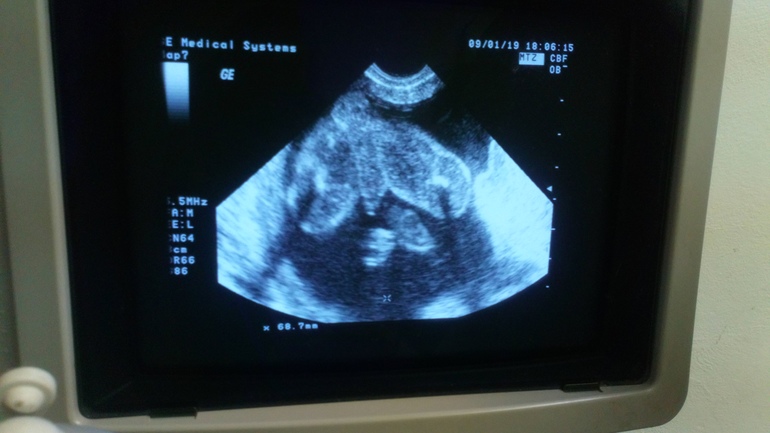

Пацан... 😍 Сан Саныч 👶🏼

УЗИ, КТГ, доплерУрааааа 🤗 сегодня прошли скрининг иииии... Пацан, у нас будет наш Сан Саныч 😎 малееький, голопопый пацан😊По скринингу вмё хорошо 🆗 шейка 38мм-это норм же? А то моя гиня пощупала мою шейку и сказала, что она коротковата. А этот момент меня, конечно, расстроил 😔

А вот и фото... Ягодички и писюнок😁